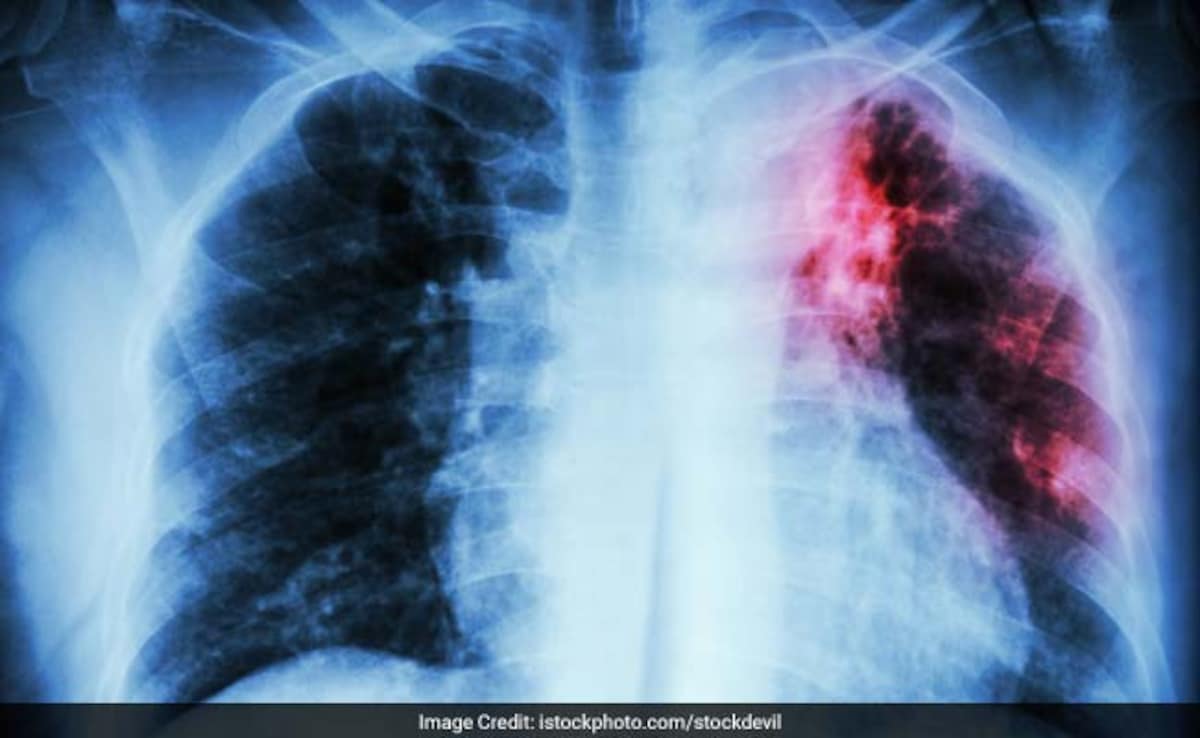

1. फेफड़ों को सीधा नुकसान

AQI 500 से ऊपर होने पर सांस की नलियों में सूजन आ जाती है. सांस फूलना, खांसी, सीने में जकड़न और दम घुटने जैसा एहसास आम हो जाता है. अस्थमा और COPD के मरीजों में अटैक का खतरा कई गुना बढ़ जाता है. लंबे समय तक ऐसी हवा में रहने से फेफड़ों की क्षमता भी कम होने लगती है.